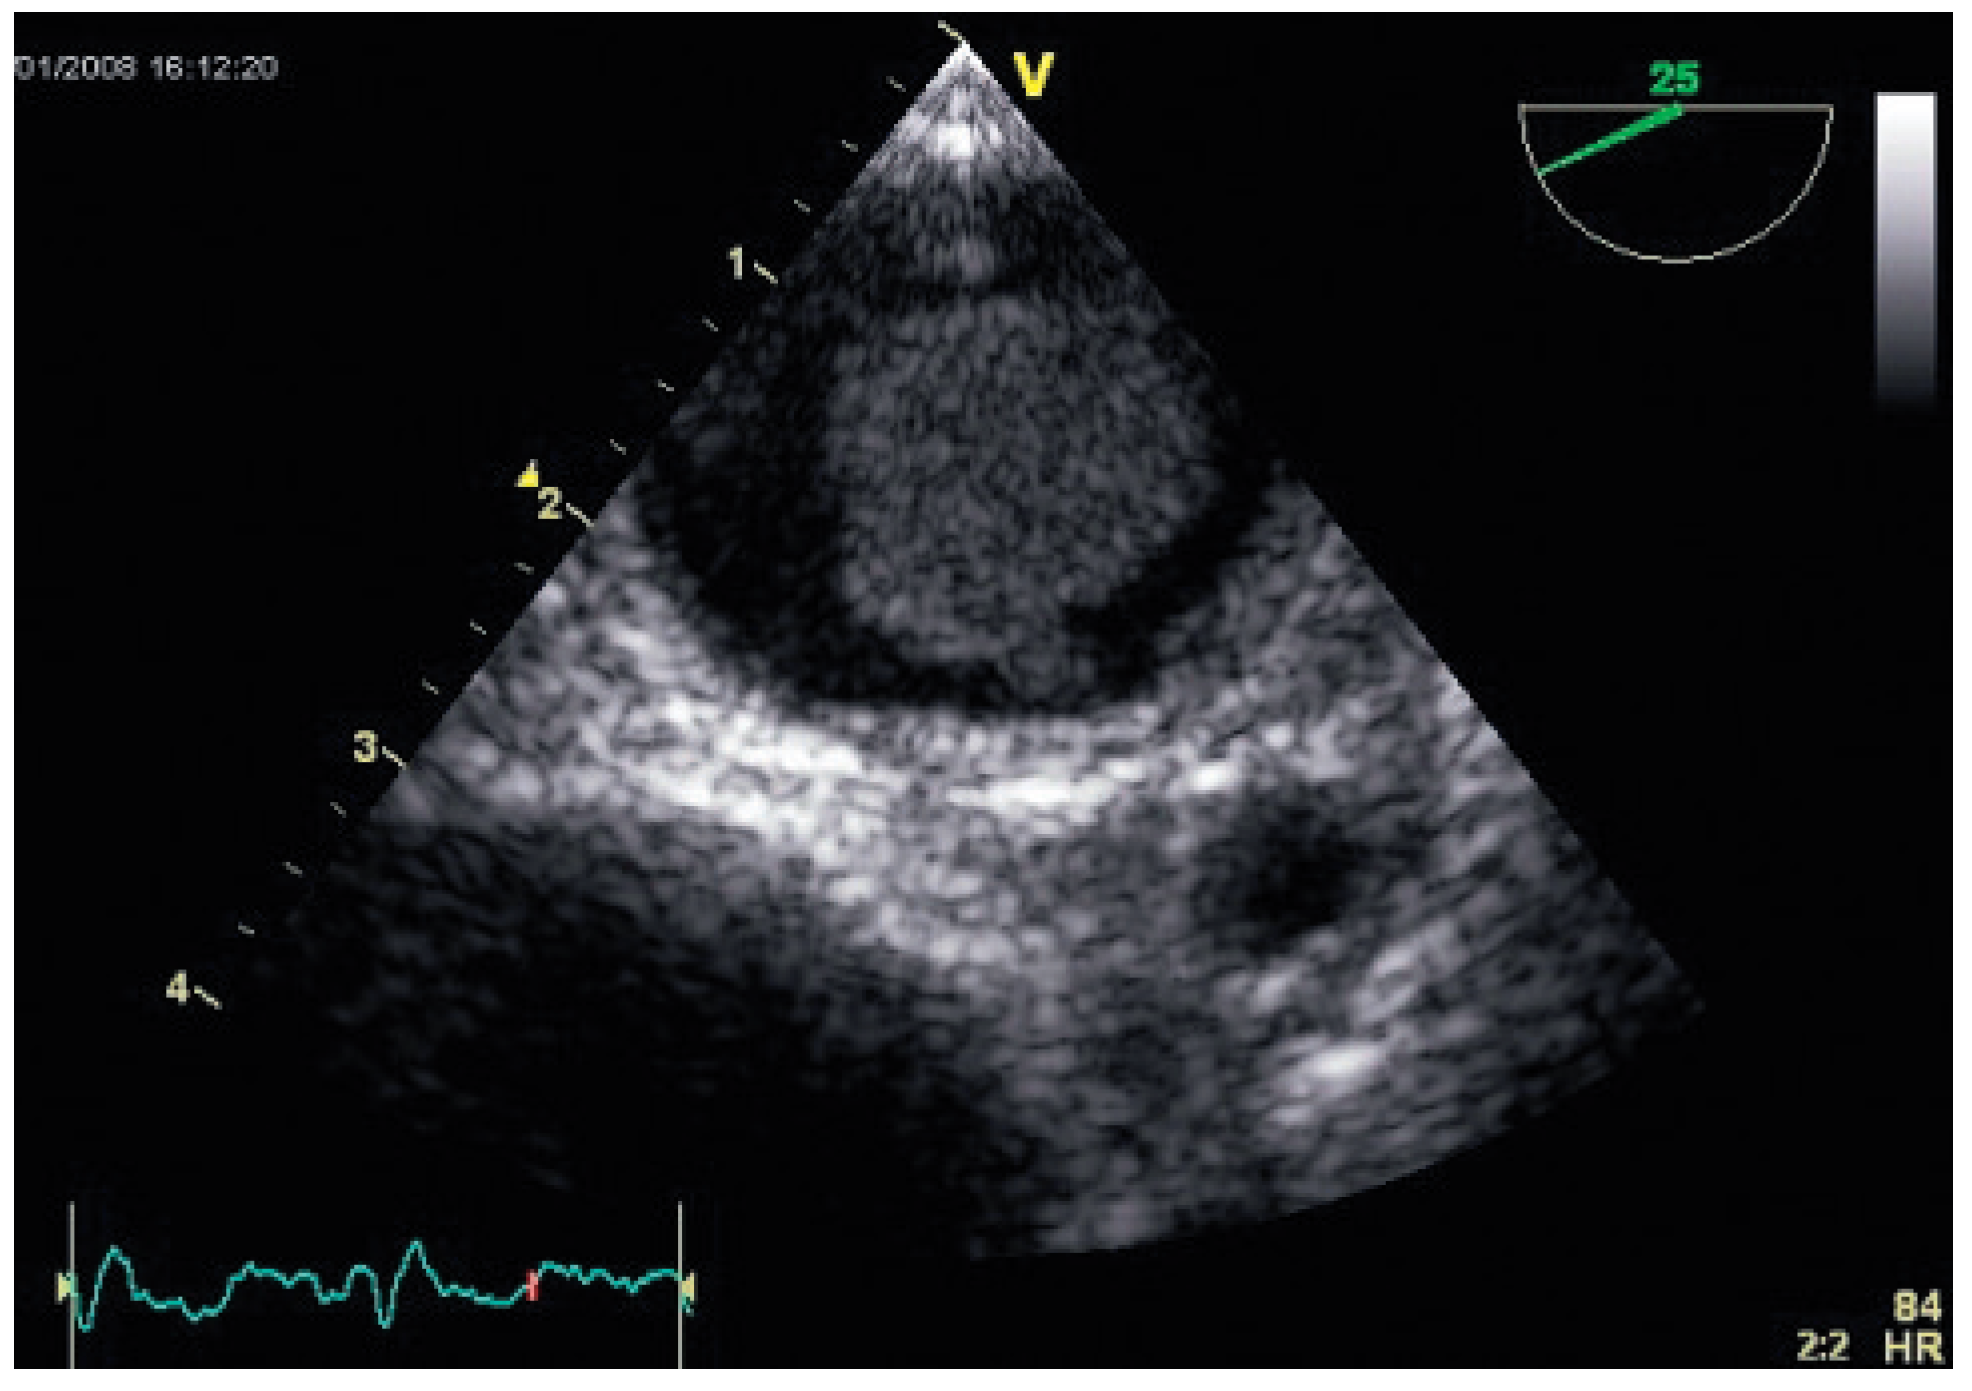

Flottierender Thrombus in der Aorta Descendens